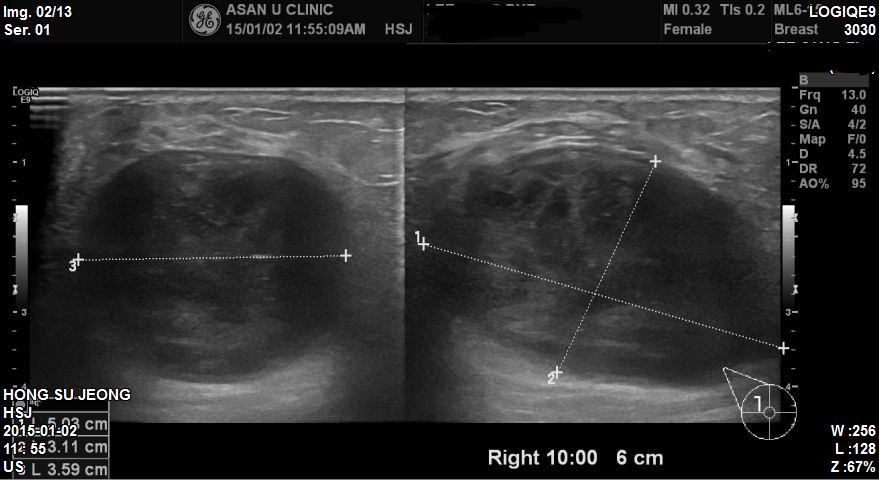

상기환자 1년전 부터 만져지던 우측유방에 혹으로 내원하심 67세 환자분이십니다

본원에서 유방초음파상 우측유방10시방향 유두에서 6cm 떨어진곳에 5.03cm의 혹이있었고

조직검사상 상피내암으로 진단되었습니다.